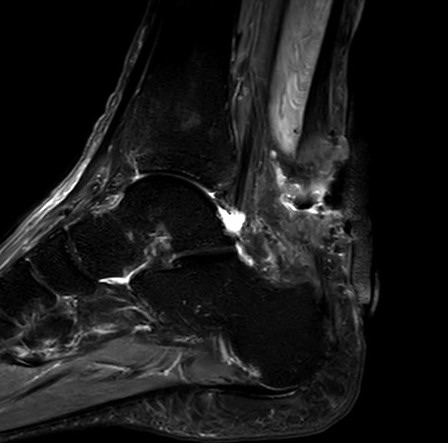

MRI

Retrocalcaneal bursitis with Haglund's

Partial tearing at insertion with retrocalcaneal bursa

Tendon thickening, Haglund's deformity and retrocalcaneal bursa